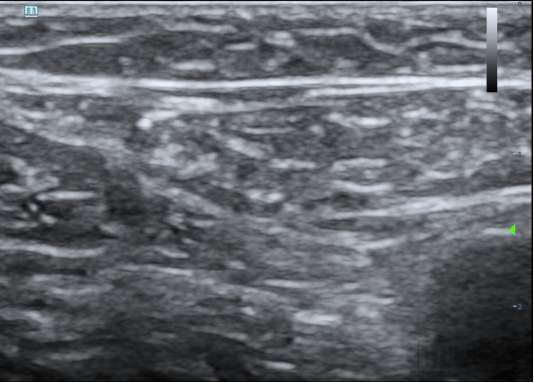

本次臨床試驗的入組患者為63歲男性,其靜脈曲張符合本臨床試驗方案入選入排標準。經(jīng)上海交通大學醫(yī)學院附屬第九人民醫(yī)院陸信武主任團隊對患者評估,選擇使用恩盛醫(yī)療自主研發(fā)的VeSeal靜脈閉合系統(tǒng),在超聲影像的引導下采用微創(chuàng)介入的方式將病變血管閉合,整個手術(shù)時間不到半小時。

據(jù)介紹,VeSeal靜脈閉合系統(tǒng)不同于其他臨床研究,VeSeal還配備了輸送導絲及導管鞘管等標準配件,注射導管在超聲下實時可見,鞘管具有標尺,手術(shù)過程無需其它配件,方便臨床醫(yī)生快速、便捷、高效的將病變血管閉合。